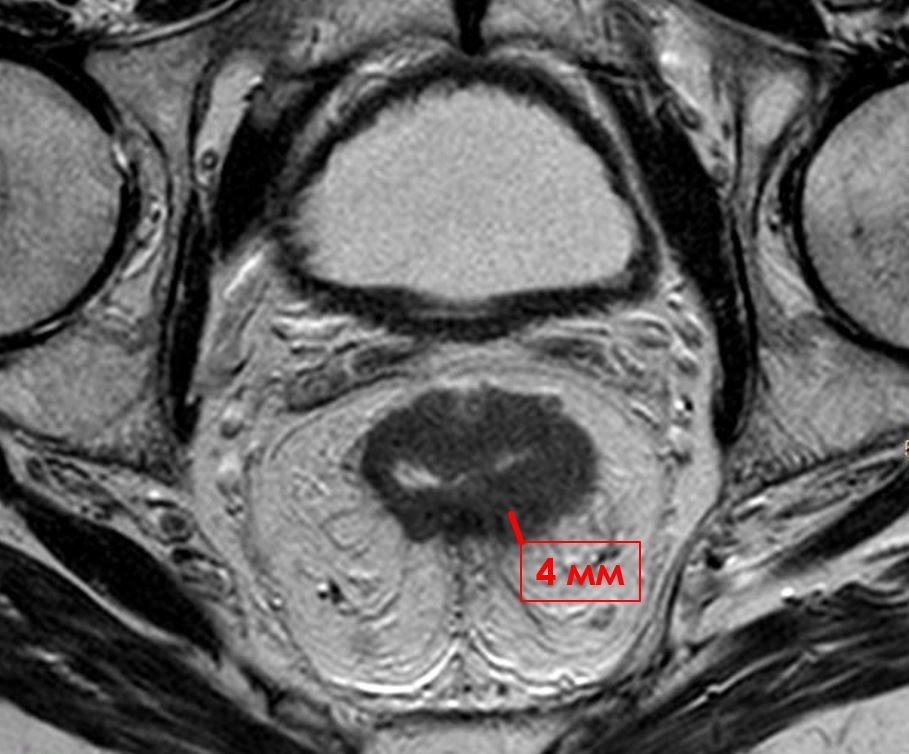

953. На мр-томограмме в среднеампулярном отделе прямой кишки выявляется циркулярная опухоль, инфильтрирующая все слои кишечной стенки и мезоректальную клетчатку на глубину до 4 мм, что по МРТ субклассификации Т3 опухоли прямой кишки соответствует